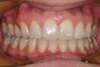

Vues pendant le traitement